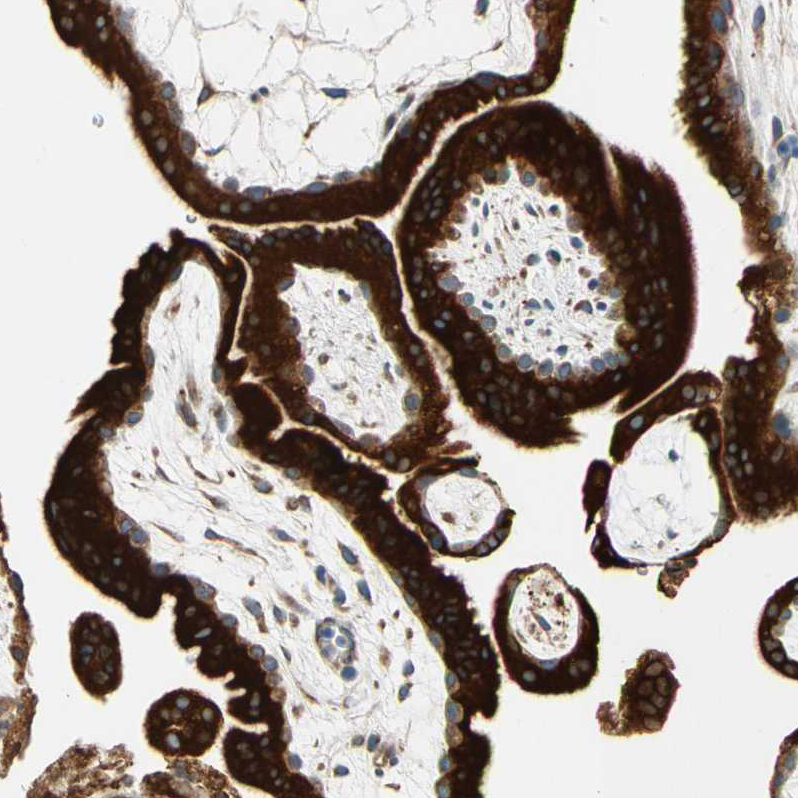

Immunohistochemical staining of human epididymis shows strong granular cytoplasmic positivity in glandular cells.